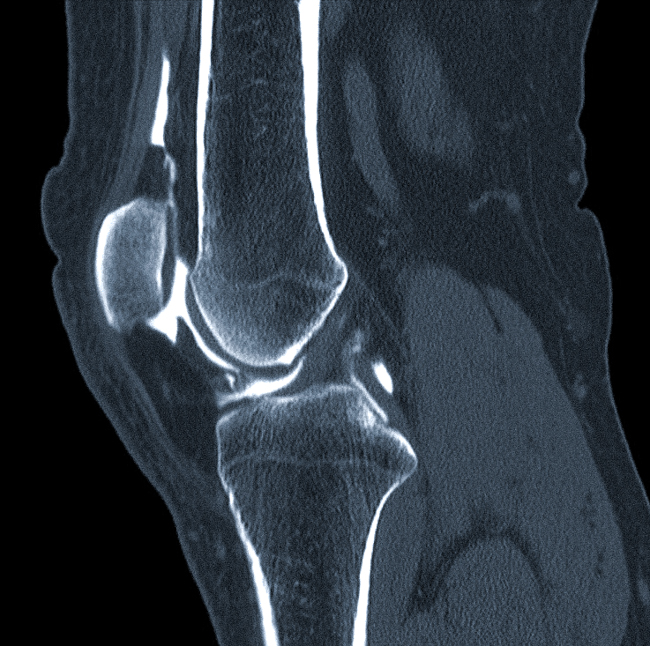

С помощью компьютерной томографии можно получить отчетливые снимки-срезы любых суставов. На снимках хорошо видны суставные поверхности, межсуставные щели, участки костей, формирующие сочленение. Менее отчетливо визуализируются мышечные ткани и связки.

Благодаря проведению томографии диагностируют патологии воспалительного, дегенеративно-дистрофического или опухолевого характера. Наиболее точно КТ суставов выявляет изменения в костных тканях, а также свежие травматические повреждения (гематомы, кровоизлияния).

Современные томографы оснащены специальными программами, позволяющими создавать трехмерные изображения исследуемой зоны. Такие данные просто незаменимы в случае предстоящего хирургического вмешательства.

Также томография может применяться для выявления или уточнения степени поражения суставных тканей при диффузных заболеваниях соединительной ткани (подагра, псориаз, склеродермия и др.). КТ коленных или тазобедренных суставов часто назначают перед эндопротезированием, от результатов исследования во многом зависит выбор импланта и способ его крепления.